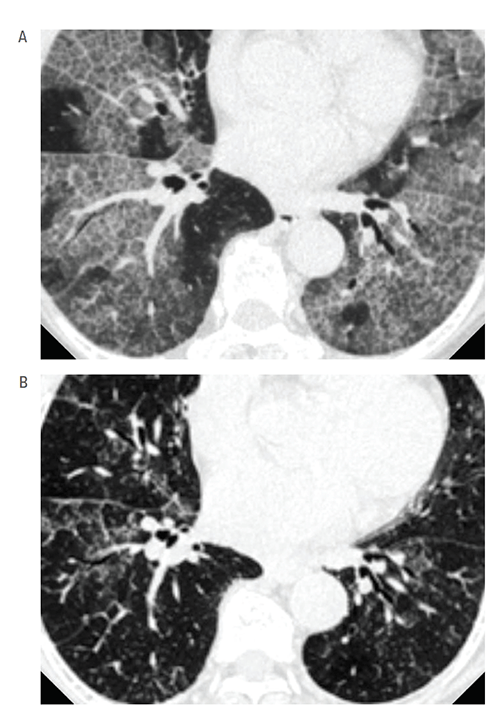

The CCTST, directed by James Heubi, MD, helps investigators produce effective study designs and competitive grant proposals. One key area is autoimmune PAP, a rare lung disease characterized by pulmonary surfactant accumulation and hypoxemic respiratory failure without FDA-approved pharmacologic therapy.

Currently, the disease is treated by whole lung lavage, an invasive procedure that requires general anesthesia, endotracheal intubation of each lung, and mechanical ventilation of one while the other is repeatedly filled with saline and drained to physically remove surfactant.